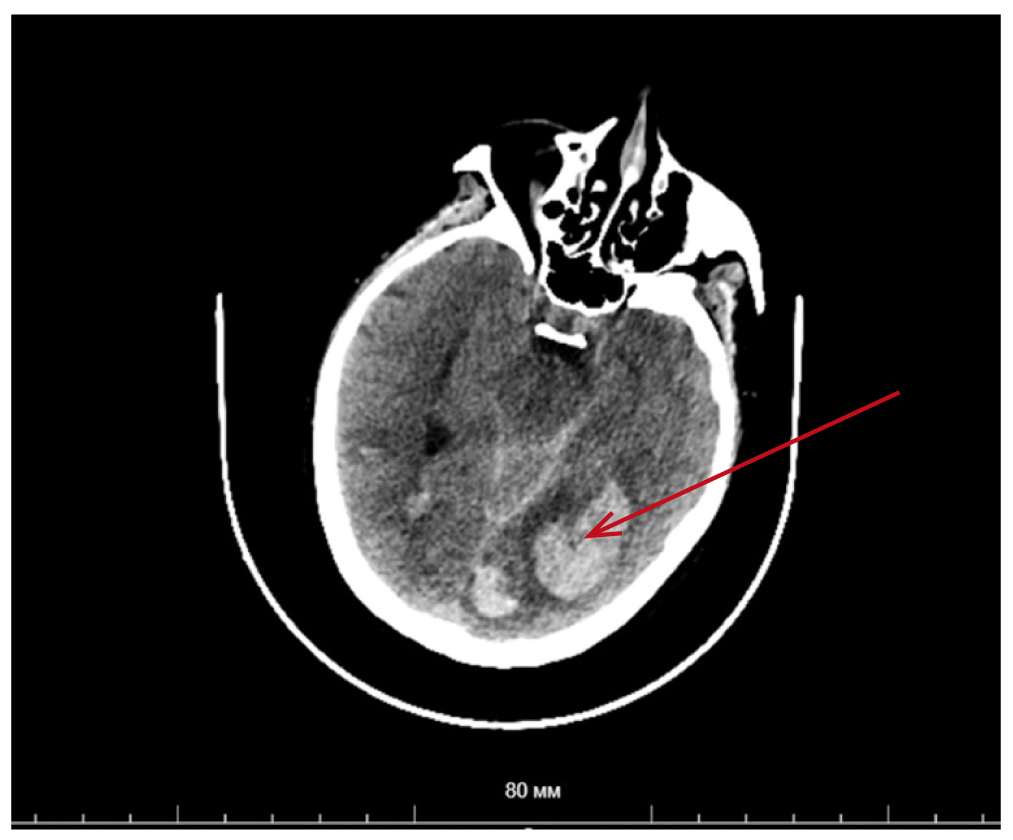

Выполнена мультиспиральная компьютерная томография головного мозга (рис. 1): паренхиматозное кровоизлияние в левую затылочную область объемом ~23 мл с прорывом в субарахноидальное пространство; в правой височной доле, правой затылочной доле, теменных долях, гемисферах мозжечка — гиперденсивные очаги с перифокальным отеком (токсоплазмоз?).

Рис. 1. Мультиспиральная компьютерная томография головного мозга пациентки Д., 41 год, с аспергиллезом центральной нервной системы: наблюдаются паренхиматозное кровоизлияние в левую затылочную область с прорывом в субарахноидальное пространство. / Fig. 1. Multispiral computed tomography of the brain of patient D., 41 years old, with aspergillosis of the central nervous system: parenchymal hemorrhage in the left occipital region with a breakthrough into the subarachnoid space is observed.